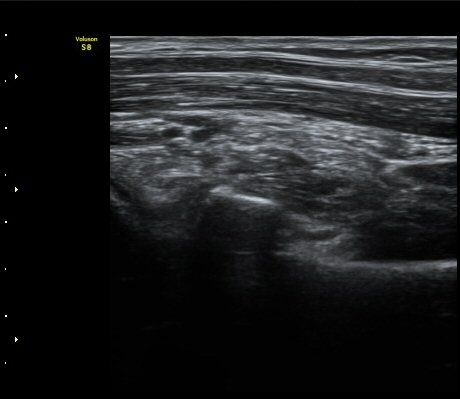

ÆÈ²ÞÄ¡ ³»Ãø¿¡¼­ ½ÃÇàÇÑ ¿ä°ñµÎ Á¾´Ü¸é°Ë»ç¿¡¼­ ¿ä°ñµÎ ÇÇÁú°ñÀÇ ºÒ±ÔÄ¥º¯È­(irregularity)°¡

°üÂûµÇ¾î ¼Õ»óÀÌ ÃßÁ¤µÊ(±×¸² 3)